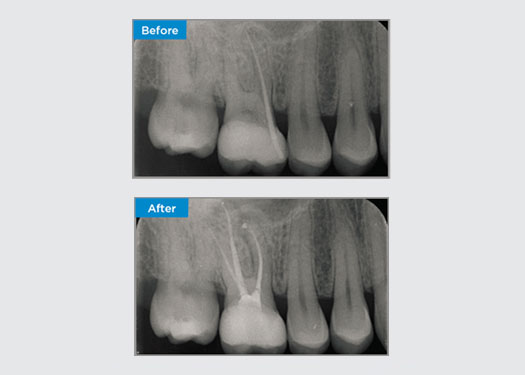

Der Patient stellte sich mit einer irreversiblen Pulpitis an Zahn 46 vor. Auf dem präoperativen Röntgenbild zeigt sich Zahn 46 mit einer zusätzlichen distalen Wurzel (Radix Entromolaris-Zahnmorphologie). Ein DVT-Scan hat das Vorhandensein einer DL-Wurzel mit starker Wurzelkrümmung bestätigt. Für diese kritische DB-Wurzel ist eine sorgfältige Feilenauswahl entscheidend.

Dr. Jack Lin, Endodontist, Sydney, NSW Australien